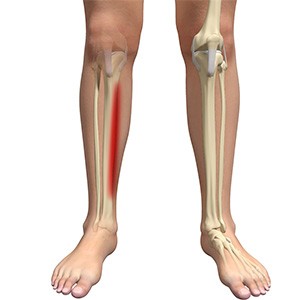

Shin Splints

Shin splints are pain and inflammation of the tendons, muscles and bone tissue along the tibia or shinbone (lower leg). It occurs because of vigorous physical activities such as exercise or sports. The condition is also referred to as medial tibial stress syndrome (MTSS).